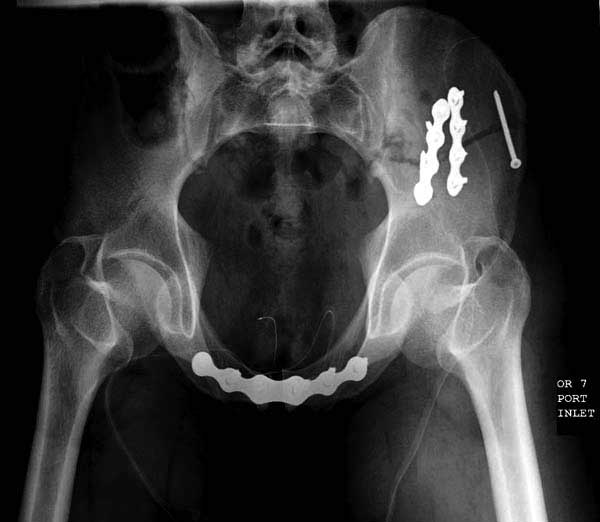

Реконструктивные пластины слабые, и для усиления необходимо установить дополнительную верхнюю пластину или оставить передний наружный фиксатор. Предпочтительным для фиксации считаю специальную для симфиза жесткую пластину из набора Joel Matta (Stryker), которая лучше, чем остальные, создает жесткость.

Здесь представлен случай 38 летнего больного (падение с высоты 9 метров) с нарушением тазового кольца. При поступлении для стабилизации передне-нижний аппарат наружной фиксации и на 6й день, вчера, операция из двух доступов.

Представлены снимки техники проведения стержней. Через место прикрепления прямой мышцы в Inferior Iliac Spine в направления вырезки создается жесткость. Weber clamp изнутри таза для репозиции, и фиксация после репозиции перелома крыла подвздошной кости. Наружный аппарат удален, нагрузка предполагается через два месяца.